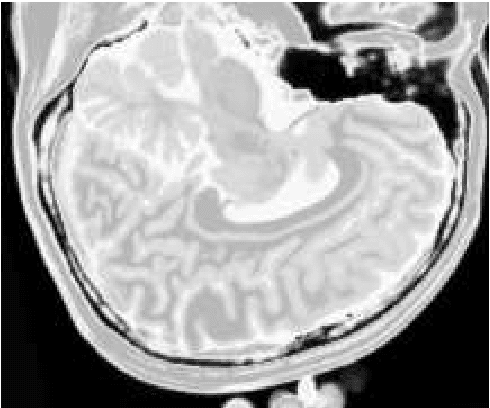

The materialist dialectical method is a philosophical investigative method to analyze aspects of reality. These aspects are viewed as complex processes composed by basic units named poles, which interact with each other. Dialectics has experienced considerable progress in the 19th century, with Hegel's dialectics and, in the 20th century, with the works of Marx, Engels, and Gramsci, in Philosophy and Economics. The movement of poles through their contradictions is viewed as a dynamic process with intertwined phases of evolution and revolutionary crisis. In order to build a computational process based on dialectics, the interaction between poles can be modeled using fuzzy membership functions. Based on this assumption, we introduce the Objective Dialectical Classifier (ODC), a non-supervised map for classification based on materialist dialectics and designed as an extension of fuzzy c-means classifier. As a case study, we used ODC to classify 181 magnetic resonance synthetic multispectral images composed by proton density, $T_1$- and $T_2$-weighted synthetic brain images. Comparing ODC to k-means, fuzzy c-means, and Kohonen's self-organized maps, concerning with image fidelity indexes as estimatives of quantization distortion, we proved that ODC can reach almost the same quantization performance as optimal non-supervised classifiers like Kohonen's self-organized maps.